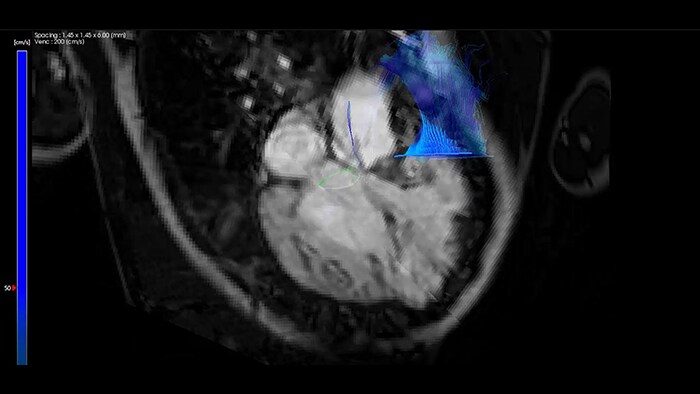

Minimally invasive congenital cardiac interventions are changing the therapeutic outcomes for young patients and for the rising number of adults with congenital heart disease (CHD). CHD presents the distinct challenge of uniquely complex pathoanatomy in some of the most vulnerable patients. Philips CHD suite is designed to adapt to your workflow needs. It provides powerful imaging to help you decide, guide, treat and confirm your interventions, while minimizing the harmful effects of radiation and contrast.[1,2]

Accomplish gentle care with powerful insights